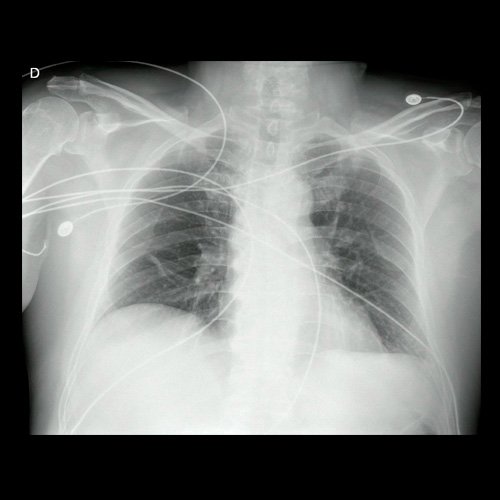

• Radiografía de tórax frente (Día 0): rotada, índice cardiotorácico conservado, senos costofrénicos libres, sin signos de consolidación.

Radiografía de tórax al ingreso (Día 0)